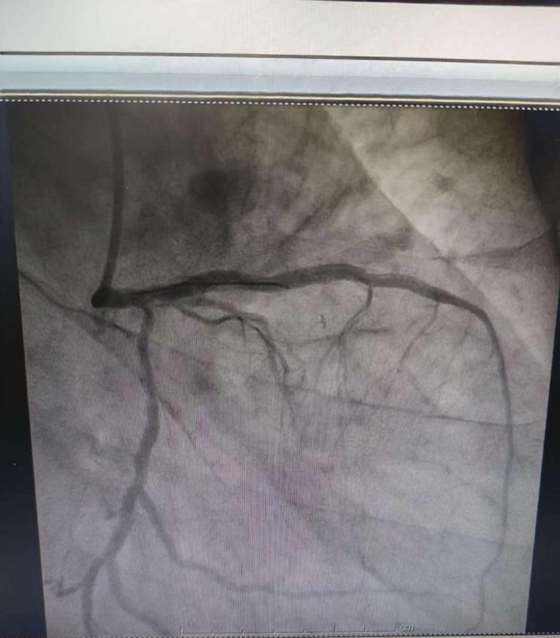

近日,湘雅常德医院心血管内科成功开展冠脉血流储备分数(FFR)精准指导冠心病介入治疗。 今年65岁的田女士,因这...